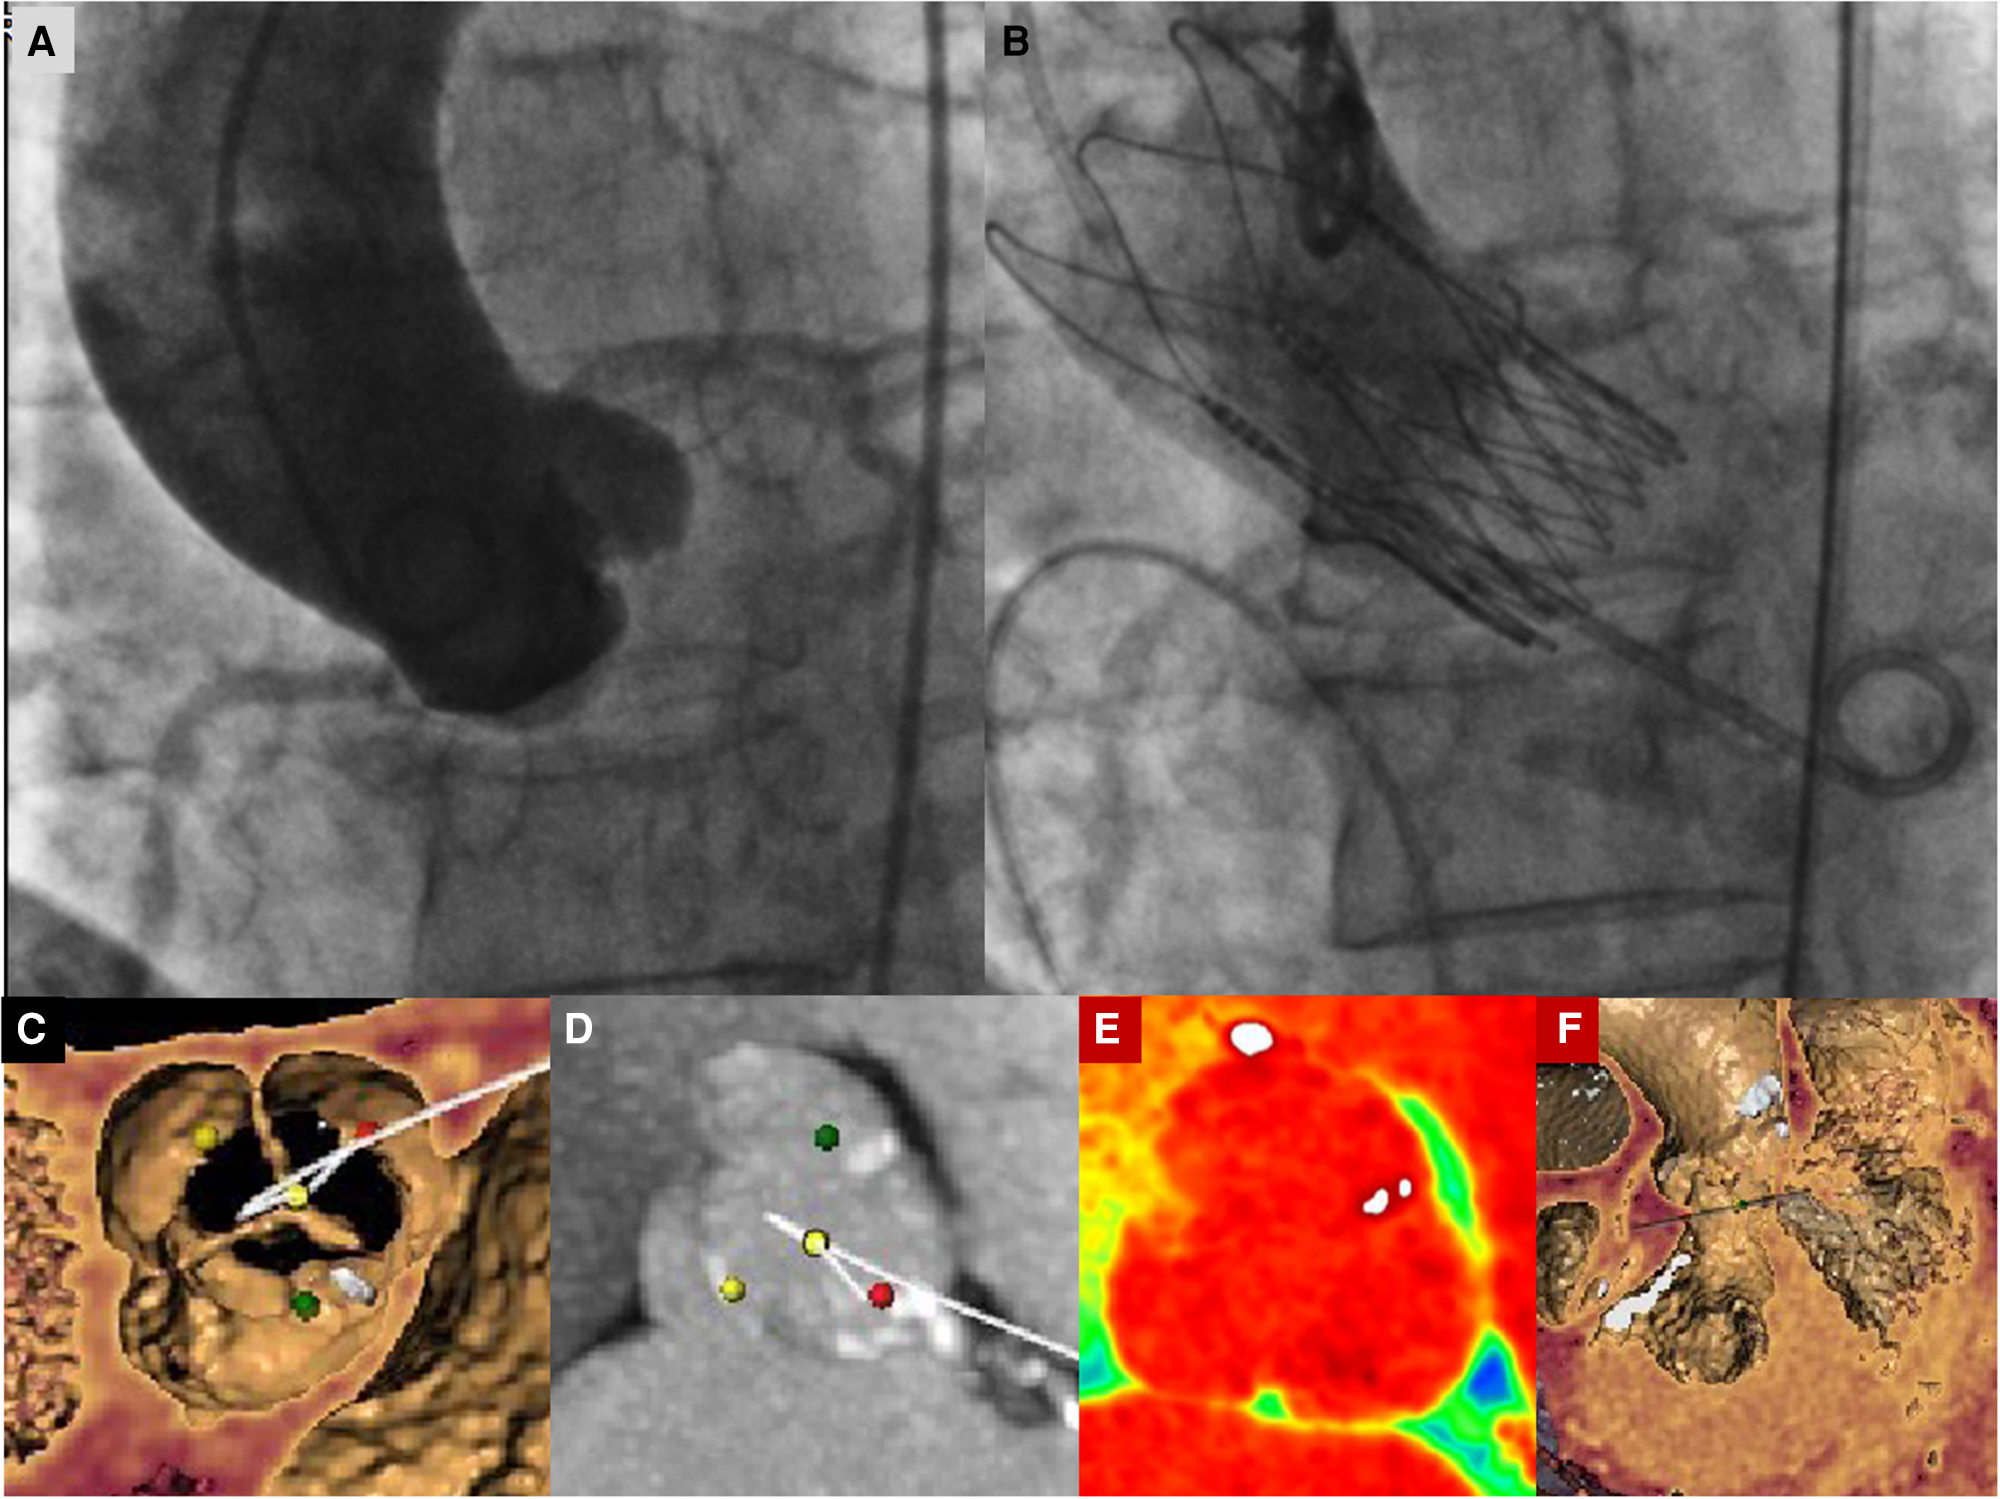

Figure 3

(A) Basal aortography in the “virtual basal plane” view (LAO 5°−10° cranial projection). (B) Final aortography documenting correct implantation of an Acurate Neo 2 small-size valve with patent coronary arteries and correct minimal LVOT protrusion of the THV to ensure anchoring without any trace of paravalvular leak. (C) Preprocedural images of CT angiography with tridimensional reconstruction of the aortic valve showing a tricuspid aortic valve. The yellow dot identifies the non-coronary cusp, the red dot identifies the left coronary cusp, and the green dot identifies the right coronary cusp. (D–F) Preprocedural images of CT angiography with tridimensional reconstruction of the aortic valve showing a tricuspid aortic valve without significant calcific degeneration and left and right ventricular chambers. In Panel (D), the yellow dot identifies the non-coronary cusp, the red dot identifies the left coronary cusp, and the green dot identifies the right coronary cusp.